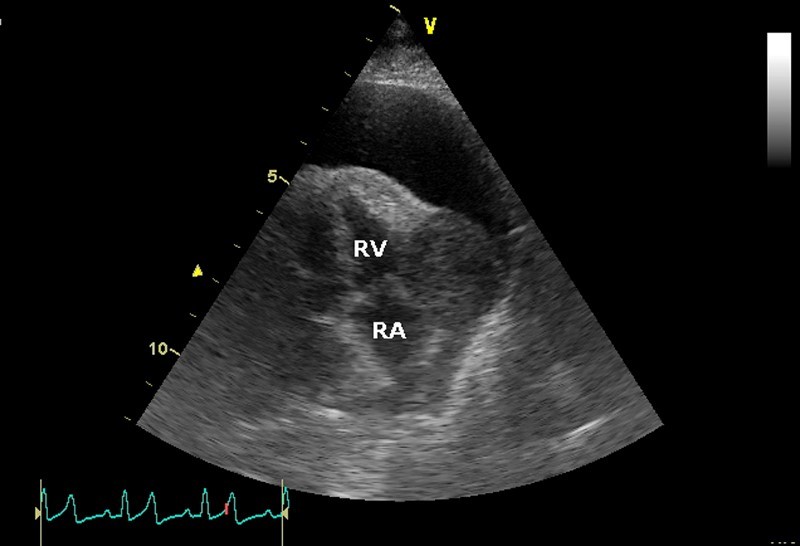

A 11-year old male castrated Golden Retriever presents for collapse with muffled heart sounds on examination. You ultrasound the heart and obtain the following image; the right atrium (RA) and right ventricle (RV) are labeled. A large mass is seen in the right atrioventricular groove with pericardial effusion. What is the likely diagnosis?

Hemangiosarcoma

The correct answer is hemangiosarcoma. Hemangiosarcoma of the heart has a predilection for the right auricle of dogs, with Golden Retrievers being predisposed. Stabilization of this patient will require pericardiocentesis; prognosis is guarded and may include chemotherapy, pericardiectomy, or rarely auriculectomy. Chemodectoma arises from the ascending aorta and heart base; lymphoma is rare in the heart of dogs and is more commonly metastatic than a single mass. Idiopathic pericardial hemorrhage is incorrect because of the clear evidence of a mass.